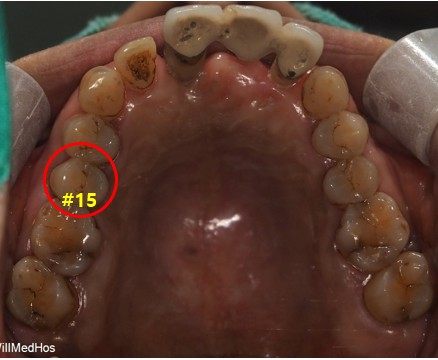

다시 환자분의 사진을 한번 보도록 하겠습니다.

상악 #15 12 11 21 치아들은 임플란트 치료를 진행했습니다.

하악 표기된 치아들은 살리는 방향으로 해서 신경치료 후 크라운 보철 치료함께 하였습니다.